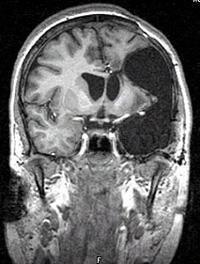

Your child may have a brain CT or MRI on the first morning after the operation to assess their brain. Caregivers will remove the surgical drains and transfer your child to a regular pediatric nursing floor after the intensive care stay.